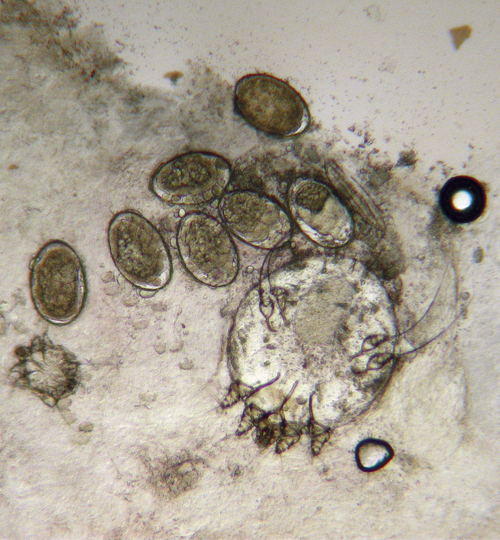

La gale – parasitose due à un acarien, Sarcoptes scabiei variété hominis – est essentiellement transmise par contact « peau à peau » rapproché et prolongé ou, plus rarement, par contact indirect via les vêtements ou la literie contaminés (notamment dans les gales profuses ou hyperkératosiques). Elle toucherait 100 à 130 millions de personnes chaque année dans le monde, sans distinction de sexe ni d’ethnie, et survient par épidémies cycliques, en particulier dans les collectivités.

Le diagnostic est essentiellement clinique. Le prurit est évocateur, d’autant qu’il existe souvent une notion de contage et de prurit familial ; il est souvent intense, généralisé, à recrudescence nocturne. Les lésions sont des vésicules, des sillons ou des nodules au niveau des espaces interdigitaux, la face antérieure des poignets, les coudes, les zones axillaires antérieures, les fesses... Chez les enfants, les vésicules ou les pustules palmoplantaires, les nodules axillaires et les lésions du visage sont fréquents.